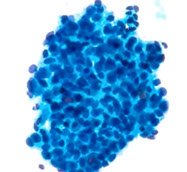

SUMP. Basaloid neoplasm

ddx: basal cell adenoma, cellular PA, AdenoCa

Cellular Basaloid neoplasm

Basal cell adenoma

aka monomorphic adenoma

- cannot distinguish clinically from PA; MC in parotid

- has mostly epithelial cells and no fibromyxoid stroma through can hav hyaline material, has various histologic growth types (solid, tubular / trabecular, papillary, and membranous)

Micro: smaller basaloid cells c inc NC ratios and scant cytoplasm in groups / cords / irreg clusters / singly c peripheral palisading in a thick nonfibrillary stroma

- squamous whorls specific though rare finding

- can have metachromatic hyaline (dark pink) stuff

Dermal analog tumor (aka membranous type basal cell adenoma) has prominent component c spheres of matrix material

- can be confused c basaloid SCC or cylindroma